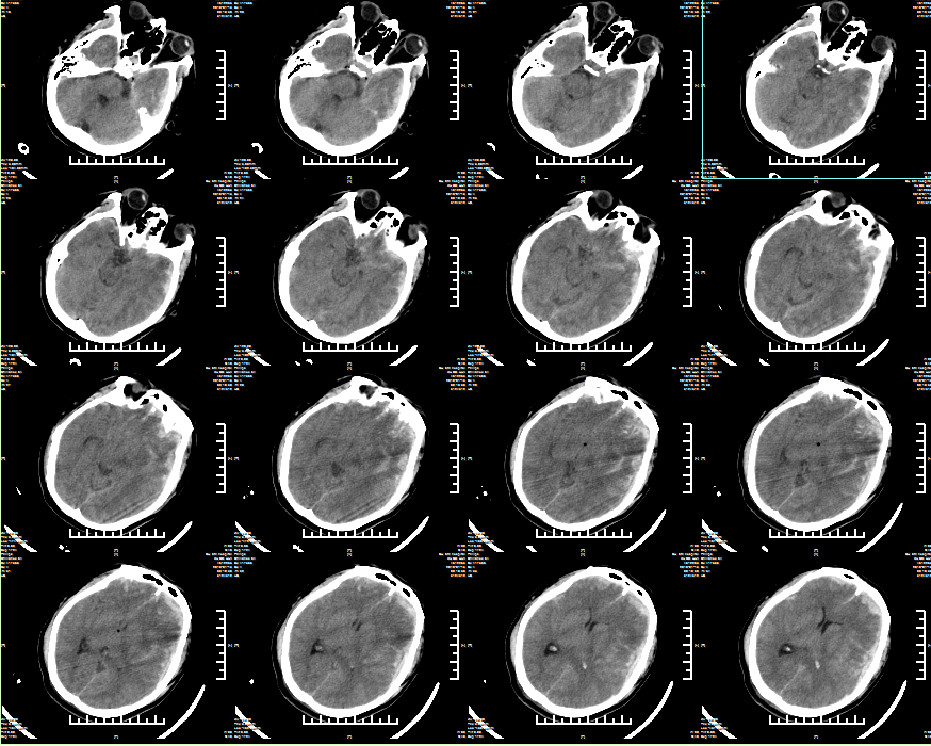

现病史:患者于入院前2小时因外伤后出现神志不清,恶心呕吐,反应迟钝,答非所问,口鼻流血,肢体无力,无肢体抽搐及寒颤高热,致本院急诊救治,头颅CT示:左额颞急性硬膜下血肿;双额颞脑挫伤;创伤性蛛网膜下腔出血;颅底骨折;颅腔积气;急诊予止血、脑保护等对症治疗措施,检查治疗期间,患者意识不清进一步加重,呼之不应,呕吐胃内容物,收入院进一步手术治疗。专科查体:昏迷, GCS 1-2-3 6分,左瞳5mm,对光反射缺失,右瞳3mm,对光反射存在,四肢痛刺激屈曲,病理征阴性。

入院诊断:双额颞脑挫伤、左额颞创伤性硬膜下血肿、创伤性蛛网膜下腔出血、颅底骨折、创伤性脑疝、左顶额骨骨折、右顶枕骨骨折。

急诊行左侧额颞顶去骨瓣减压术+血肿清除术+颅内压监护探头置入术。术后ICP6-9mmHg。

术后常规复查头颅CT(2019年1月15日9点54分):右顶硬膜外出血急诊行右顶硬膜外血肿清除术。

二次术后常规复查头颅CT(2019年1月15日16点04分)